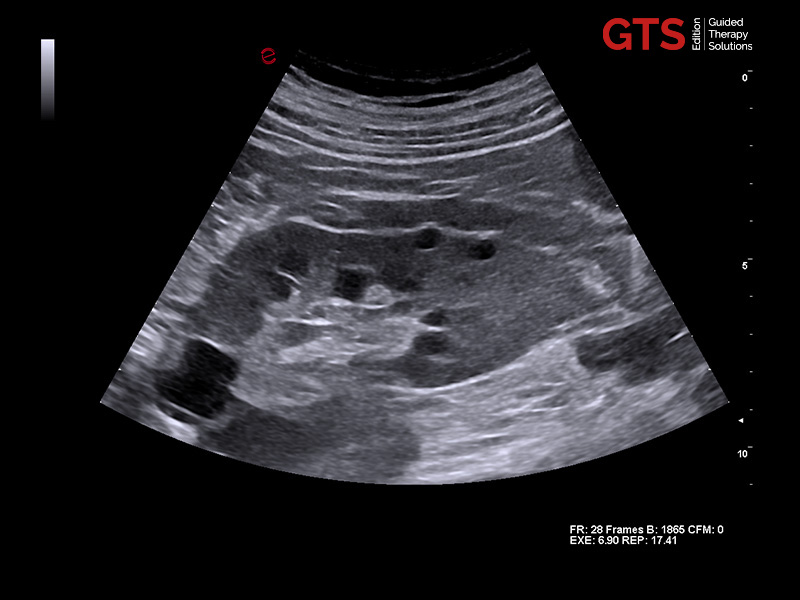

Prostate in axial view using E 3-12 - End-fire probe, E 3-12

Prostate in sagittal view using TLC 3-13 - Bi-planar probe, TLC 3-13